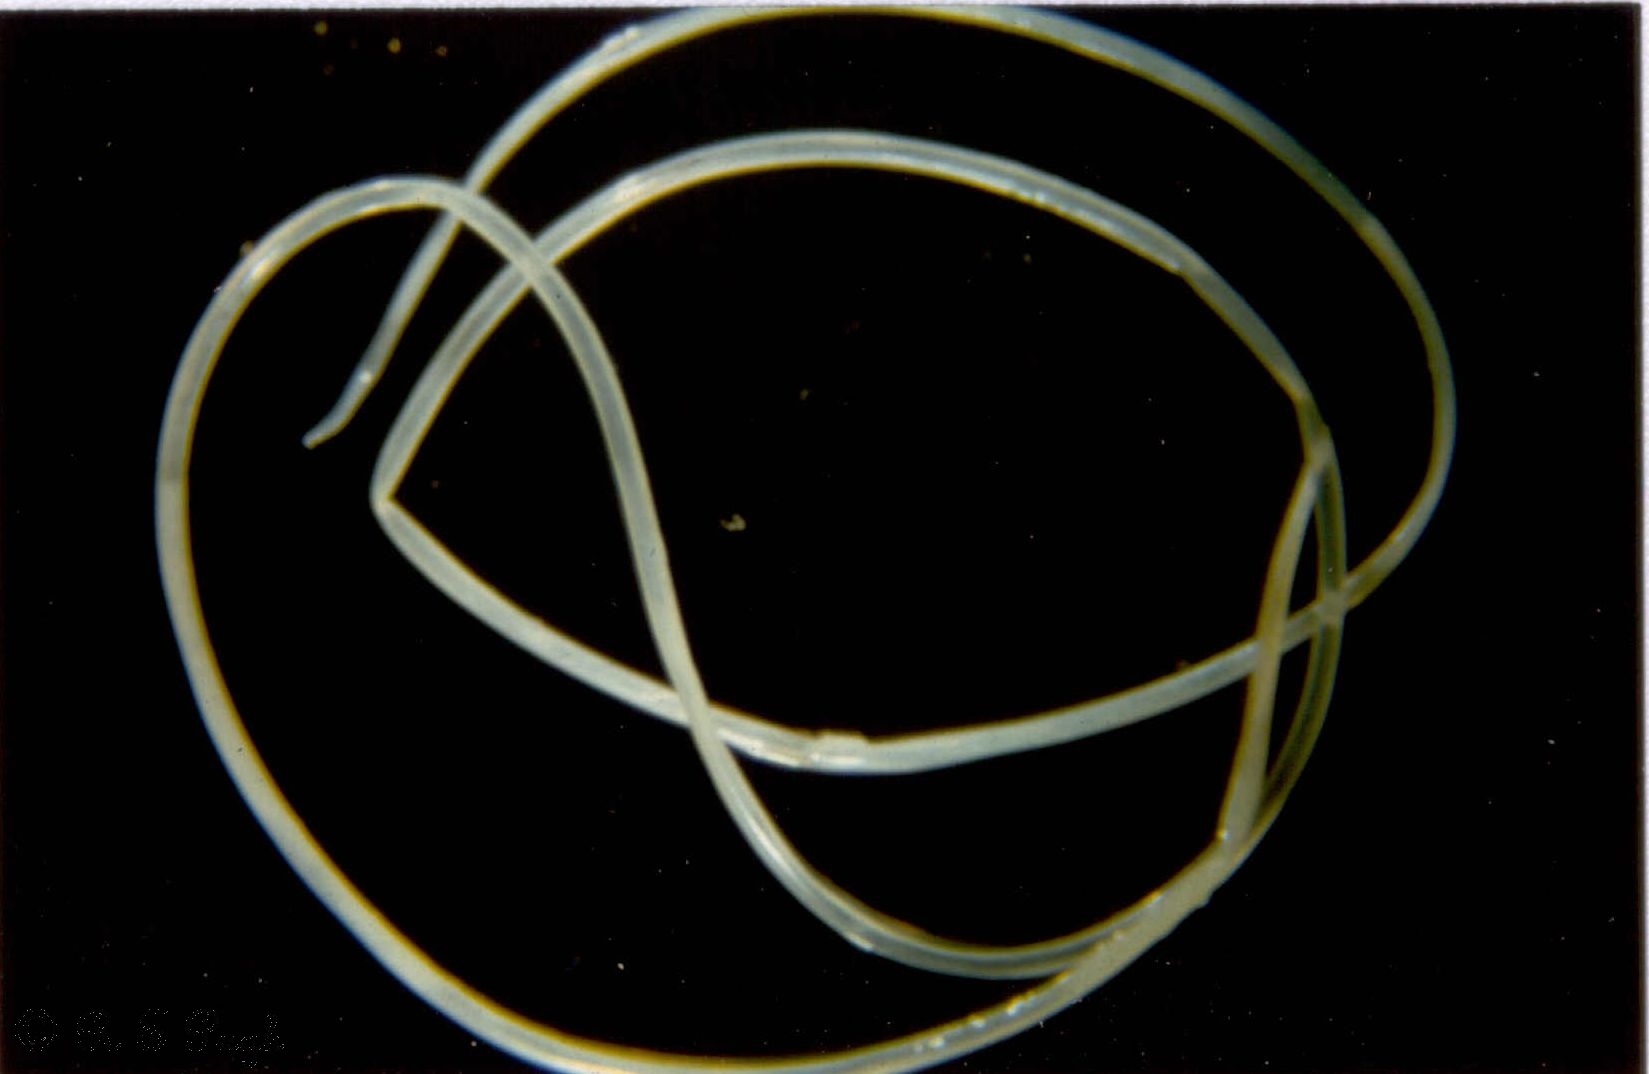

A ragadozók szívférgességét a Dirofilaria immitis nevű fonálféregfaj okozza. A féreg kifejlett egyedei átlagosan 12-30 cm hosszúak, főként a szívben és a tüdő ereiben élősködnek. A betegség korábban jellemzően a trópusi, szubtrópusi területeken volt elterjedt, hazánkban legfeljebb csak ilyen területen nyaraló családok kutyáinál diagnosztizálták. Az első itthon fertőződött kutyáról 2009-ben számoltak be. Az elmúlt 2-3 évben ugrásszerűen megnőtt a hazai esetek száma. Sok olyan kutya betegedett meg vagy bizonyult fertőzöttnek szűrővizsgálatokkal, akik nemhogy az ország, de sokszor még a település határát sem lépték át. Sajnos a kórokozó már jelen van hazánkban is, és mivel súlyos, nem ritkán halálos kimenetelű betegséget okozhat kutyánkban, kiemelt figyelmet kell fordítanunk az ellene történő védekezésre.

Kép: parasite.org.au